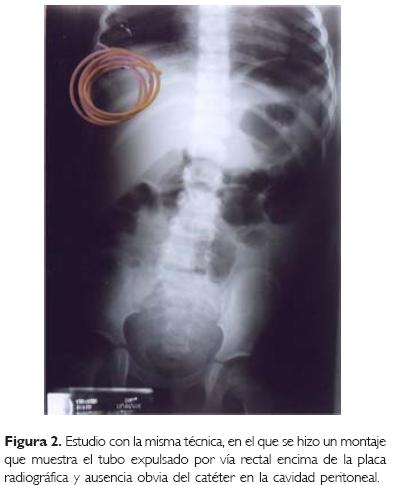

Femenino de cuatro años de edad que procede de la Ciudad de México, y en la que se refiere el antecedente de infección del sistema nervioso central por Haemophylus influenzae al año de edad, lo que le ocasionó como complicación la formación de un higroma subdural frontoparietal bilateral. Ocho días después de identificado el problema se le efectuó una derivación subaracnoideoperitoneal con un catéter de silastic (Medtronic, Minneapolis, Minnesota USA). La evolución fue aparentemente desfavorable ya que reingresó 10 días después por convulsiones tónicoclónicas generalizadas. Dentro de la unidad se le efectuó estudio radiológico simple de abdomen, encontrándose como hallazgo la migración casi completa del catéter hacia la cavidad peritoneal, por lo que éste se rescató a través de una incisión en piel y se recolocó una semana después en el otro lado. A los seis meses de ser egresada, nuevamente fue hospitalizada en su unidad de origen por cuadro similar al anterior. Se le realizó un estudio radiológico de control (Fig. 1) en donde se observó migración completa del catéter, motivo por el cual es enviada para su extracción al Departamento de Cirugía de nuestra unidad a la que acude con el catéter en una bolsa de plástico y totalmente asintomática. En esa ocasión se le practicó radiografía de abdomen y encima de ésta se colocó el catéter que recién había expulsado (Fig. 2).